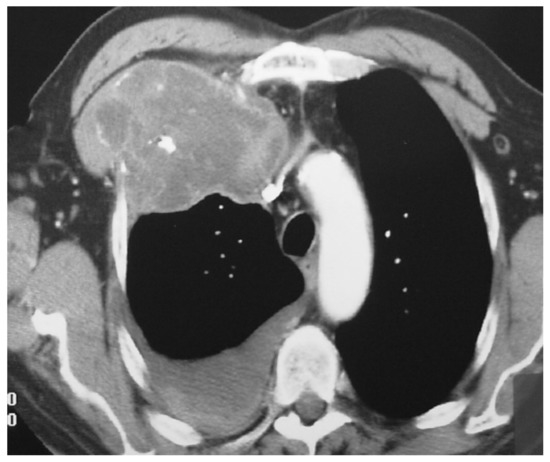

| Tumor location | Costochondral junction | 9/11 (82%) | 10/15 (67%) | 0.804 | 19/26 (73%) |

| Sternum | 2/11 (18%) | 4/15 (27%) | 6/26 (23%) | ||

| Posterior rib | 0/11 (0%) | 1/15 (6%) | 1/26 (4%) | ||

| Tumor size | Mean in mm (range) | 56 (31–151) | 57 (20–127) | 0.435 | 57 (20–151) |

| Median in mm (range) | 40 (31–151) | 46 (20–127) | 45 (20–151) | ||

| Character | Lytic only | 0/11 (0%) | 3/15 (20%) | 0.238 | 3/26 (12%) |

| mixed | 11/11 (100%) | 12/15 (80%) | 23/26 (88%) | ||

| Chondroid Matrix | 0–25% | 5/11 (45%) | 10/15 (67%) | 0.551 | 15/26 (58%) |

| 25–50% | 4/11(36%) | 3/15 (20%) | 7/26 (27%) | ||

| 50–75% | 1/11 (9%) | 2/15 (13%) | 3/26 (12%) | ||

| 75–100% | 1/11 (9%) | 0/15 (0%) | 1/26 (4%) | ||

| Tumor location within the bone | Central | 5/11 (45%) | 7/15 (47%) | 1.000 | 12/26 (48%) |

| peripheral | 6/11 (55%) | 8/15 (53%) | 14/26 (52%) | ||

| Soft tissue mass | No | 3/11(27%) | 1/15 (7%) | 0.279 | 4/26 (15%) |

| Yes | 8/11(73%) | 14/15 (93%) | 22/26 (85%) |